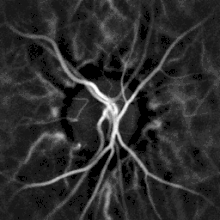

Remote, indirect monitoring of blood flow by laser Doppler

Noninvasive hemodynamic monitoring of eye fundus vessels can be performed by Laser Doppler holography, with near infrared light. The eye offers a unique opportunity for the non-invasive exploration of cardiovascular diseases. Laser Doppler imaging by digital holography can measure blood flow in the retina and choroid, whose Doppler responses exhibit a pulse-shaped profile with time[38][39] This technique enables non invasive functional microangiography by high-contrast measurement of Doppler responses from endoluminal blood flow profiles in vessels in the posterior segment of the eye. Differences in blood pressure drive the flow of blood throughout the circulation. The rate of mean blood flow depends on both blood pressure and the hemodynamic resistance to flow presented by the blood vessels.